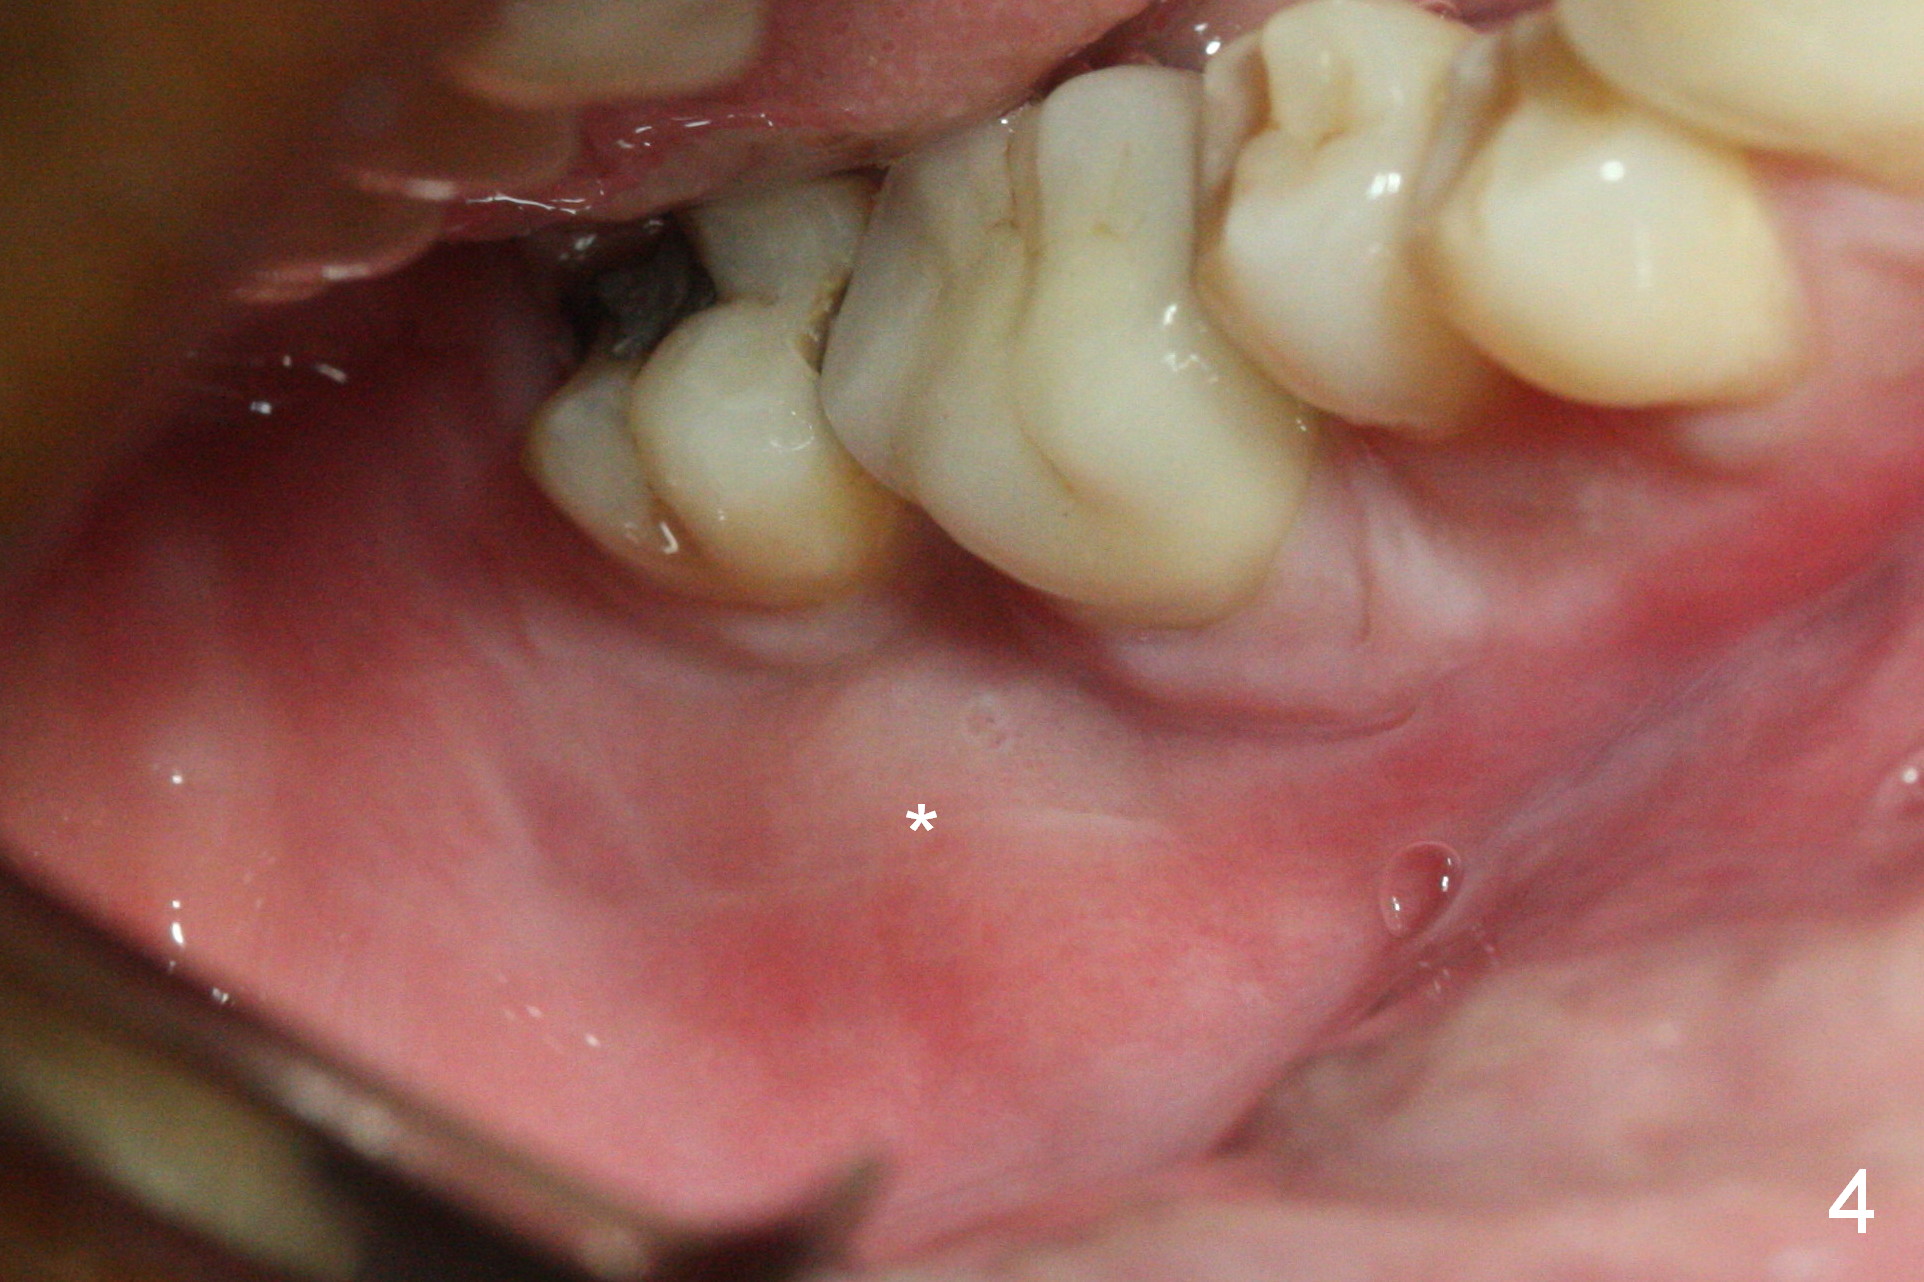

A 49-year-old man develops acute abscess of the lower right quadrant (Fig.3-5) secondary to periimplantitis at #30 (Fig.1,2,6). The latter is probably due to buccal placement (Fig.6 (*: buccal plate)). After removal of the infected implant, an osteotomy is established as lingual as possible using single drill modality (Fig.7 (4.3 mm Magic Drill after 1.6 mm pilot drill and Marking Bur, then Final Drill). With the single drill, the osteotomy does not shift buccally in spite of the lower buccal plate. A 5x9 mm IBS implant is placed lingually as planned (Fig.8 (>40 Ncm)), followed by an angled abutment (5 mm x 15° (4 mm)) (Fig.9 A). The buccal gap is filled with autogenous bone, allograft (.5-1.5 mm) and Osteogen (Fig.10 *), covered by resorbable and non-resorbable membranes. After suturing, periodontal dressing is applied.